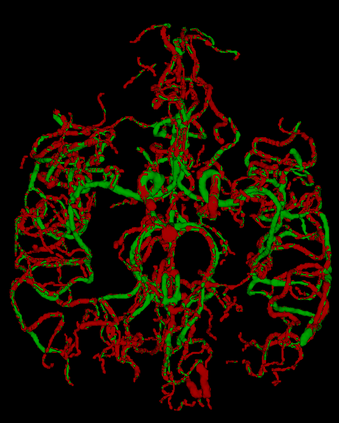

Vessel segmentation is an essential task in many clinical applications. Although supervised methods have achieved state-of-art performance, acquiring expert annotation is laborious and mostly limited for two-dimensional datasets with a small sample size. On the contrary, unsupervised methods rely on handcrafted features to detect tube-like structures such as vessels. However, those methods require complex pipelines involving several hyper-parameters and design choices rendering the procedure sensitive, dataset-specific, and not generalizable. We propose a self-supervised method with a limited number of hyper-parameters that is generalizable across modalities. Our method uses tube-like structure properties, such as connectivity, profile consistency, and bifurcation, to introduce inductive bias into a learning algorithm. To model those properties, we generate a vector field that we refer to as a flow. Our experiments on various public datasets in 2D and 3D show that our method performs better than unsupervised methods while learning useful transferable features from unlabeled data. Unlike generic self-supervised methods, the learned features learn vessel-relevant features that are transferable for supervised approaches, which is essential when the number of annotated data is limited.